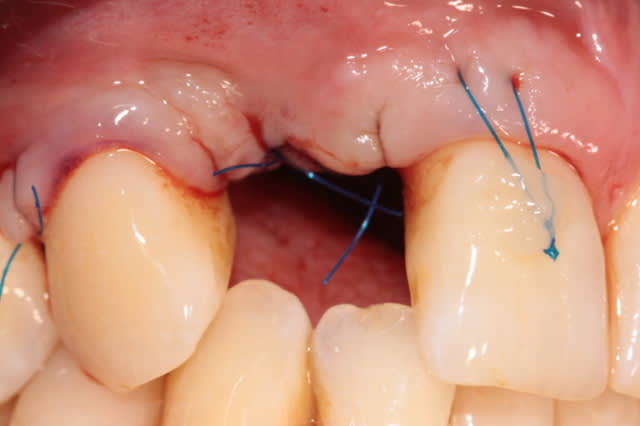

j'ai un cas similaire qui cicatrise et puisque que l'on parlait de recouvrement gingival, voilà un cas où j'espère un résultat sympa... en tout cas c'est prometteur

1 et 2 pré op

3 6 semaines après extraction

4,5,6 intervention avec pilier et barre titane

7 3 semaines post chir à la dépose des points